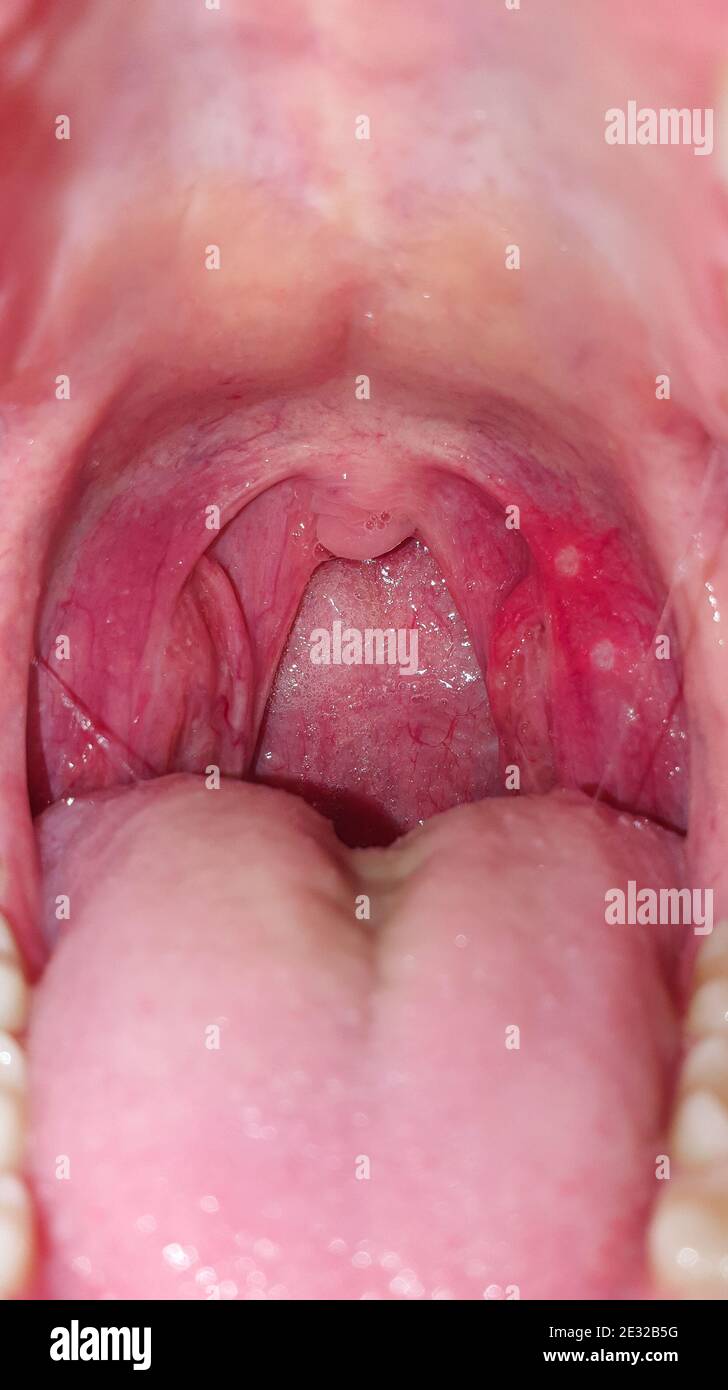

Halsschmerzen im Mund, Nahaufnahme. Erkrankungen des Rachens und der Schleimhaut, Rötung der Kehle und Mandeln, das Phänomen der Stomatitis und Stockfotohttps://www.alamy.de/image-license-details/?v=1https://www.alamy.de/halsschmerzen-im-mund-nahaufnahme-erkrankungen-des-rachens-und-der-schleimhaut-rotung-der-kehle-und-mandeln-das-phanomen-der-stomatitis-und-image397735116.html

Halsschmerzen im Mund, Nahaufnahme. Erkrankungen des Rachens und der Schleimhaut, Rötung der Kehle und Mandeln, das Phänomen der Stomatitis und Stockfotohttps://www.alamy.de/image-license-details/?v=1https://www.alamy.de/halsschmerzen-im-mund-nahaufnahme-erkrankungen-des-rachens-und-der-schleimhaut-rotung-der-kehle-und-mandeln-das-phanomen-der-stomatitis-und-image397735116.htmlRF2E32B5G–Halsschmerzen im Mund, Nahaufnahme. Erkrankungen des Rachens und der Schleimhaut, Rötung der Kehle und Mandeln, das Phänomen der Stomatitis und